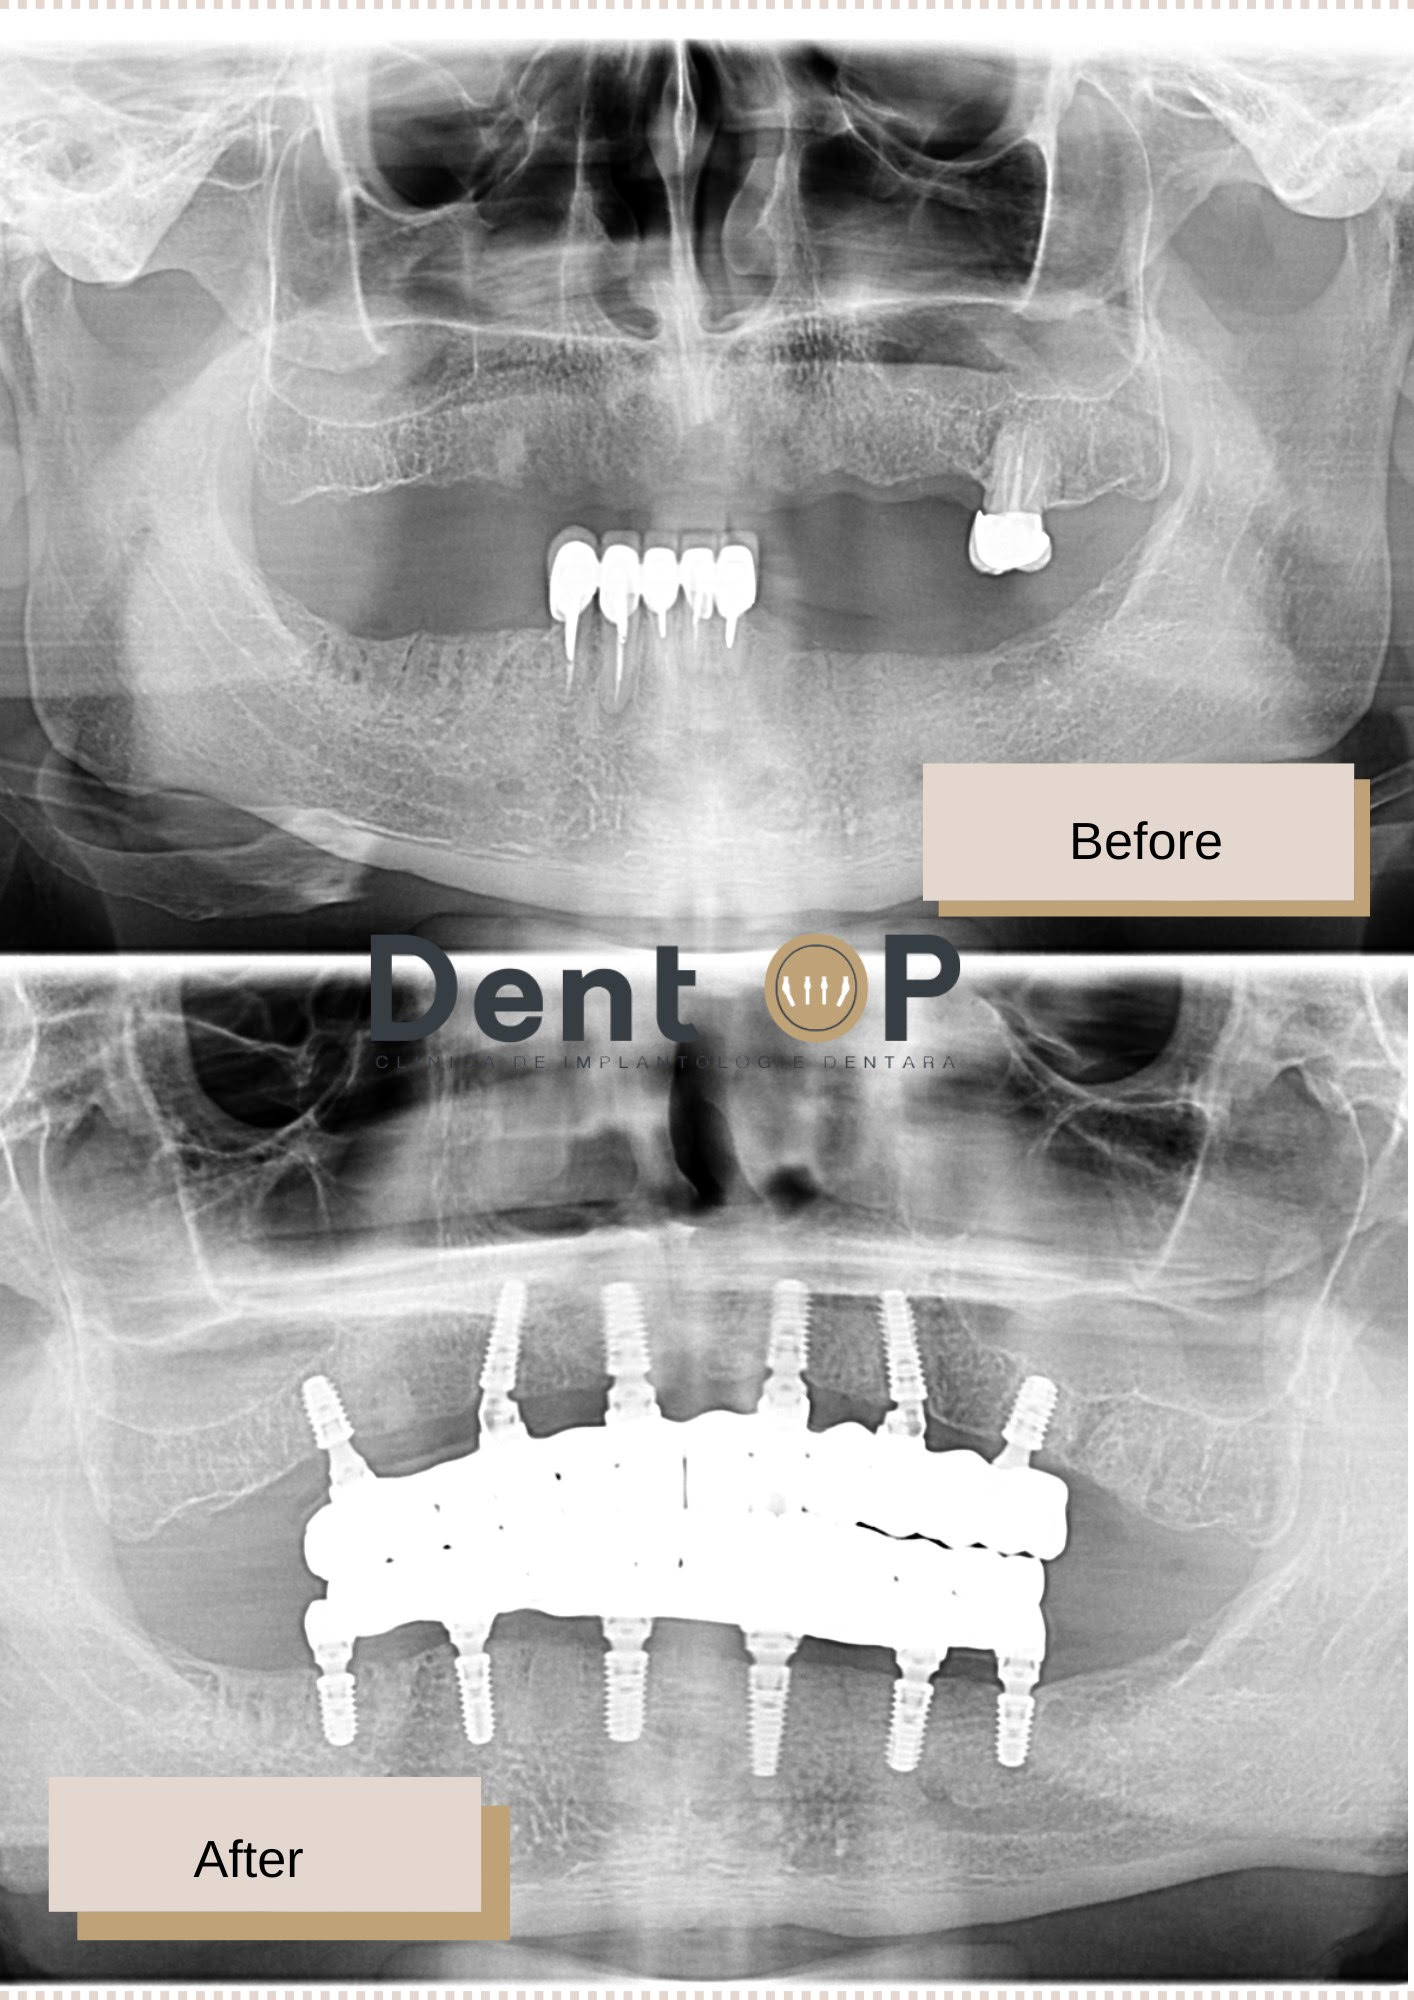

Domnul S. este unul dintre pacienții care nu a mai putut purta placa mobilă și a decis înlocuirea acesteia cu implanturi dentare. Astfel, a căpătat o dantură fixă cu care poate mânca și își poate relua viața socială.

Domnul S. și-a făcut curaj să vină la clinica noastră, iar după consultația cu Dr Cazacu Corrado Cazacu a decis că procedura ,,Dantură Fixă în 24h pe implanturi dentare” este soluția ideală pentru a putea zâmbi din nou cu încredere.

După 4-6 luni de la intervenția cu 12 implanturi dentare inserate, domnul S. a beneficiat si de lucrările finale. Cu o estetică superioară și o funcționalitate sporită, dantura finală l-a ajutat pe domnul S. să aibă un zâmbet nou și încrezător.